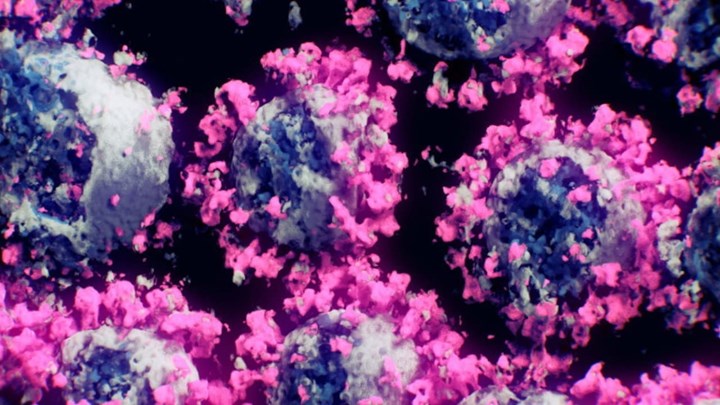

Οι ιοί SARS-CoV-2 φωτογραφήθηκαν για πρώτη φορά. Ερευνητές από την αυστριακή εταιρεία Nanographics, παρακλάδι του Τεχνικού Πανεπιστημιίου της Βιέννης, χρησιμοποίησαν νέες τεχνικές και δημιούργησαν εικόνες 3D του πραγματικού ιού SARS-CoV-2, από κατεψυγμένα δείγματά του.

Αυτό είναι το πιο ακριβές μοντέλο του ιού SARS-CoV-2 το οποίο δημιούργησαν επιστήμονες της Nanographics σε συνεργασία με τα ερευνητικά κέντρα του Πανεπιστημίου Επιστημών και Τεχνολογίας “Βασιλιάς Αμπντουλάχ” της Σαουδικής Αραβίας, του Scripps Research καθώς και με το Τεχνικό Πανεπιστήμιο της Βιέννης.

Σύμφωνα με την Bild, έγινε εκχύλιση άθικτων σωματιδίων του ιού SARS-CoV-2 σε δείγματα και μετά σάρωση με κρυο-ηλεκτρονική μικροσκοπία (Cryo-EM) η οποία είναι τεχνική ηλεκτρονικής μικροσκοπίας που εφαρμόζεται σε δείγματα που ψύχονται σε κρυογονικές θερμοκρασίες και “βομβαρδίζονται” από ηλεκτρόνια. Η εκτροπή των ηλεκτρονίων λόγω αλληλεπίδρασης με το δείγμα δίνει μια εικόνα της δομής του του ιού. Αυτές οι νέες μέθοδοι θα επιτρέψουν στο μέλλον την ανάλυση των βιολογικών μικροσκοπικών δεδομένων πιο εύκολα και γρήγορα, υποστηρίζουν οι ερευνητές.